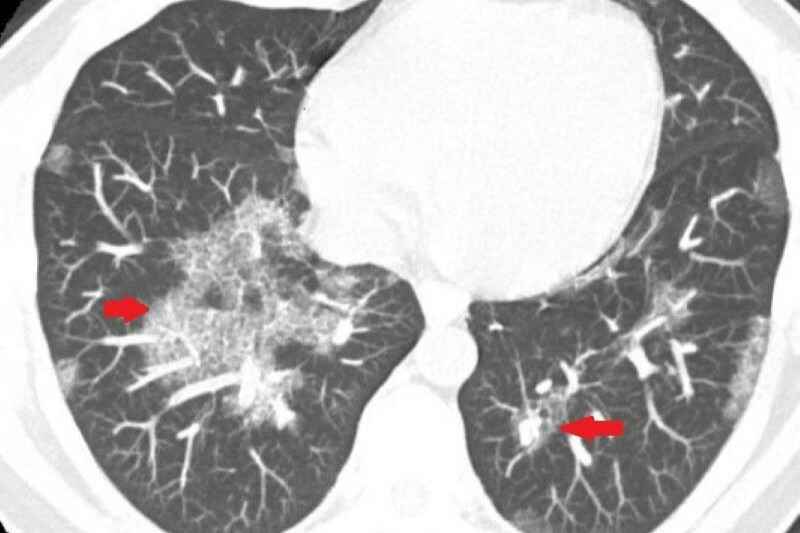

醫療團隊從電腦斷層初判魏先生為肺部慢性發炎,但透過支氣管鏡檢查顯示,氣道清晰無異常,細菌與黴菌等培養檢查也呈現陰性,病因成謎,只能密切追蹤病況,3個月後發現患者雙肺白影惡化,最後進行肺部穿刺切片,確診為極罕見的肺部蛋白質沉積症。

他表示,人在正常情況下,肺部會分泌表面張力素等蛋白質,協助肺泡維持張開、促進氣體交換,但當蛋白質異常累積,且無法被自然代謝清除,就會堵塞肺泡,導致缺氧、呼吸困難,嚴重時可能危及生命。此疾病早期常無明顯症狀,容易與肺炎、肺纖維化等疾病混淆,導致誤診與治療延誤。